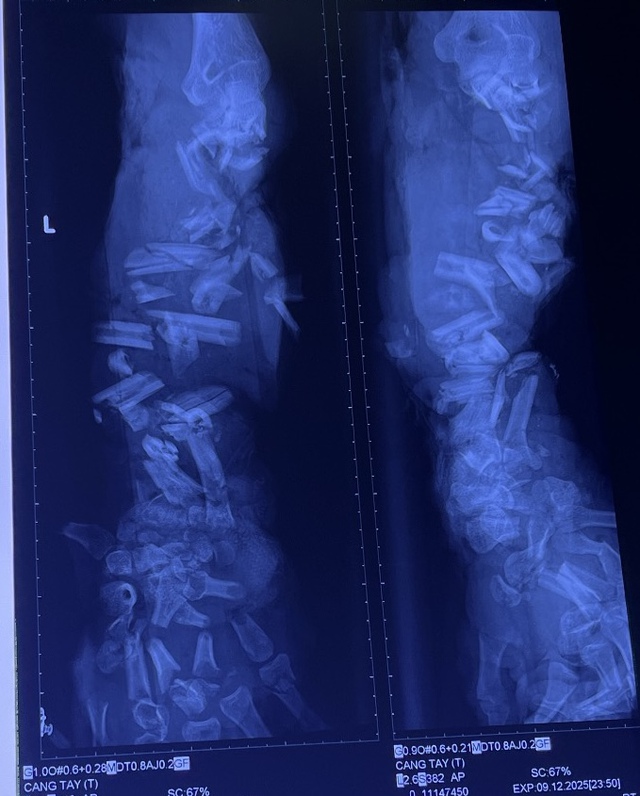

Bệnh nhân đến cấp cứu với tình trạng vết thương dập nát phức tạp rất nặng cánh tay trái (từ cẳng tay đến bàn tay) do máy nghiền vỏ dừa. Xương tay nát đứt nhiều khúc, mô mềm dập nát nặng, tím tái, dính nhiều đất cát và dầu nhớt.

Hình ảnh phim X - quang cho thấy xương cẳng tay và bàn tay trái của bệnh nhân bị gãy từng khúc, không còn hình dạng của xương quay và xương trụ